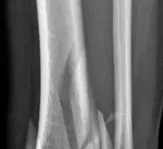

كسور البيلون هي كسور معقدة تصيب الجزء السفلي من عظم الساق (قصبة الساق) وتؤثر على مفصل الكاحل. يتضمن علاجها عادةً التدخل الجراحي لتثبيت الكسر واستعادة وظيفة المفصل، متبوعًا ببرنامج تأهيل مكثف لضمان الشفاء التام وتقليل المضاعفات، تحت إشراف خبير مثل الأستاذ الدكتور محمد هطيف.